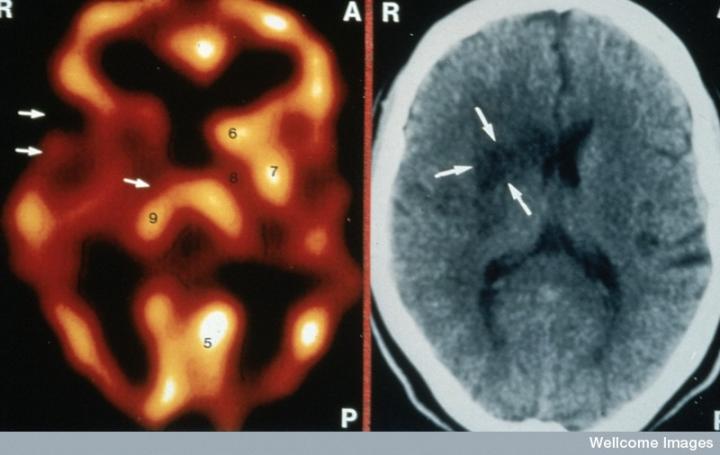

CT掃描的主圖顯示左側有一些中風損傷,由 Wellcome Images提供。Wellcome Photo Library提供的慢性中風的附加圖像 ,Wellcome Images,QL 從胚胎干細胞培養(yǎng)的神經(jīng)元。Ying & A. Smith, Wellcome Images 和 Yirui Sun, Wellcome Images 移植的小鼠神經(jīng)干細胞。